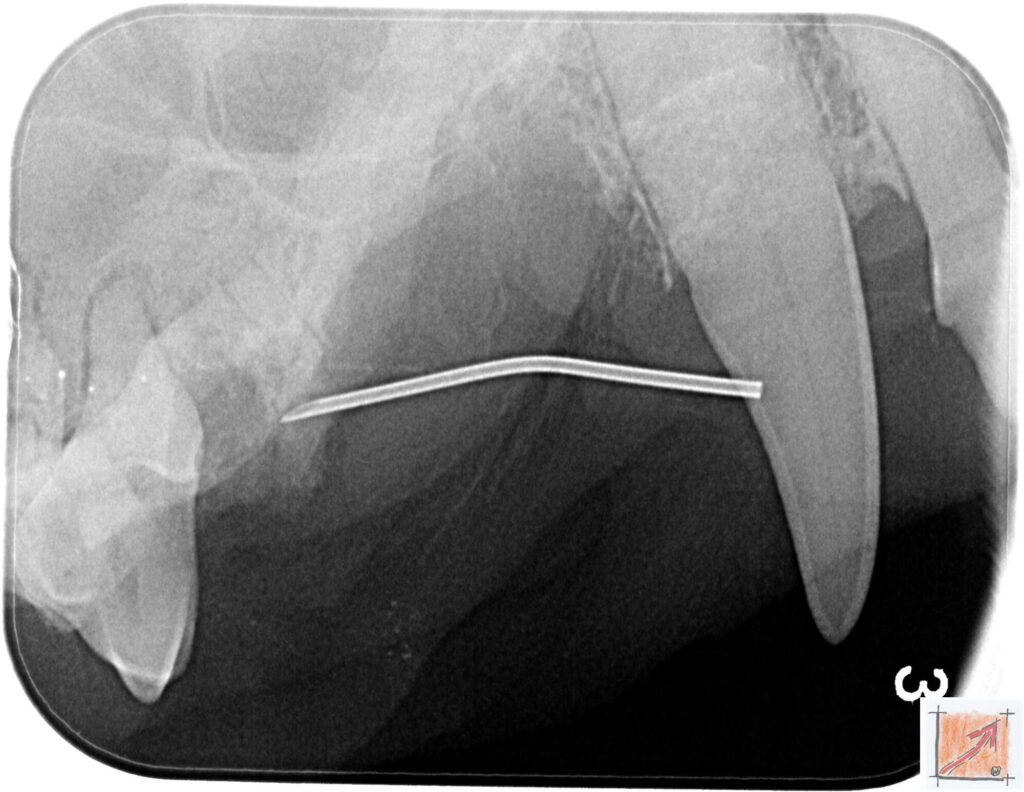

Röntgenbilder vom Thierrischen Orakel bei der Zahn-OP:

Warum Dentalröntgen beim Chihuahua lebenswichtig ist:

Ein Blick hinter die Kulissen von Chihuahua-Zähnen:

In dieser Galerie zeigen wir exklusive intraorale Röntgenaufnahmen einer Zahn-Operation beim Thierrischen Orakel als Chihuahua vom BauFachForum. Während oberflächlicher Zahnstein oft sichtbar ist, verbirgt sich die wahre Gefahr für das Herz meist unter dem Zahnfleischsaum.

Das digitale Dentalröntgen ist der Goldstandard in der modernen Tiermedizin, um parodontale Entzündungsherde und Wurzelabszesse sicher zu diagnostizieren. Für Chihuahuas wie dem Thierrischen Orakel, mit Mitralklappeninsuffizienz ist dieser diagnostische Schritt essenziell. Nur wenn versteckte Bakterienherde an der Zahnwurzel oder mit dem Fachbegriff Apikalabszesse erkannt und saniert werden, kann das Risiko einer bakteriellen Endokarditis oder einfach ausgedrückt einer Herzinnenhautentzündung minimiert werden.

Unsere Aufnahmen von Patienten dem Thierrischen Orakel verdeutlichen den Unterschied zwischen einer rein optischen Zahnreinigung und einer medizinisch fundierten Sanierung unter Röntgenkontrolle.

Chihuahua Mitralklappeninsuffizienz Trachealkollaps:

Wichtig ist im Vorfeld die Zahnhygiene des Chihuahuas. Die Bilder zeigen Dentale Röntgenbilder vom Thierrischen Orakel als Chihuahua-Hund während seiner Zahn-OP. Darstellung von Kieferknochen und Zahnwurzeln zur Diagnose von Parodontitis.

Zahnröntgenaufnahme bei Chihuahua Thierry:

Untersuchung der Zahnwurzeln auf Entzündungsherde als Prophylaxe gegen bakterielle Endokarditis.

Intraorales Dentalröntgen eines Chihuahuas:

Die Bilder zeigen Zähne und Wurzelstrukturen im Unterkiefer zur Planung einer Extraktion bei hochgradigem Zahnstein.